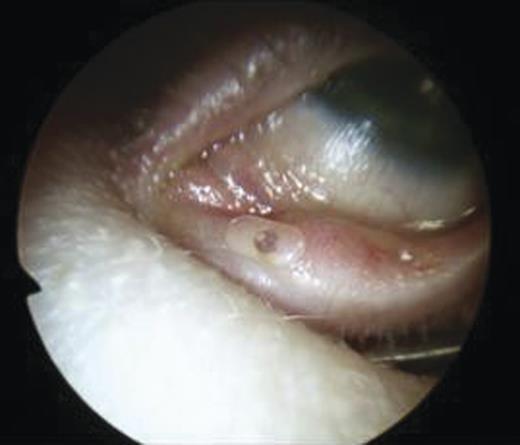

Clinical examination revealed a small cystic swelling in her left medial canthus (Fig. 1). There was no discharge on pressure, mild tenderness was elicited and the swelling was not compressible. The rest of the eye examination was normal with a visual acuity of 6/6 in both eyes.

The puncti were probed (Fig. 5) and fluorescein dye instilled with no dye outflow to the left inferior meatus. It was not possible to pass the probe through the upper punctum so a mini-monoka DCR stent was inserted and secured (Figs. 6 and 7). Chloramphenicol eye drops were instilled.